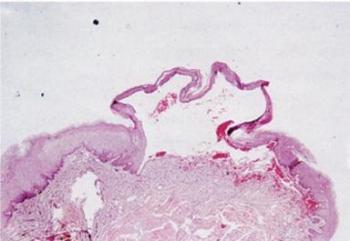

1.8. ábra. Subepithelialis bulla alakul ki, ha a hám elválik az alatta lévő kötőszövettől (corium)

(J.A. Regezi, J.J. Sciubba, R.C.K.Jordan. Oral Patholgy, Saunders, Elsevier , St. Louis. 2008)